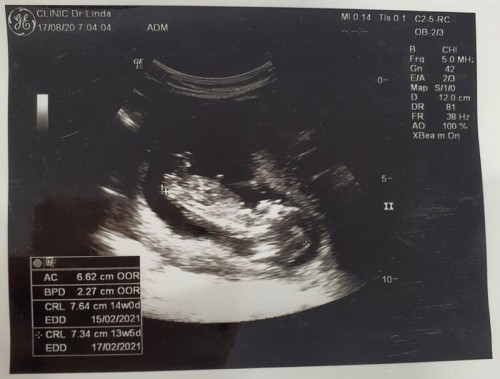

13W 5d ตัวโตไหมคะ ? หนูตัวยาว 7.34 cm

ส่วนน้ำหนักแม่ขึ้นมาแค่ 0.6 kg.เองค่ะ ก่อนท้องหนัก 49.6 kg.